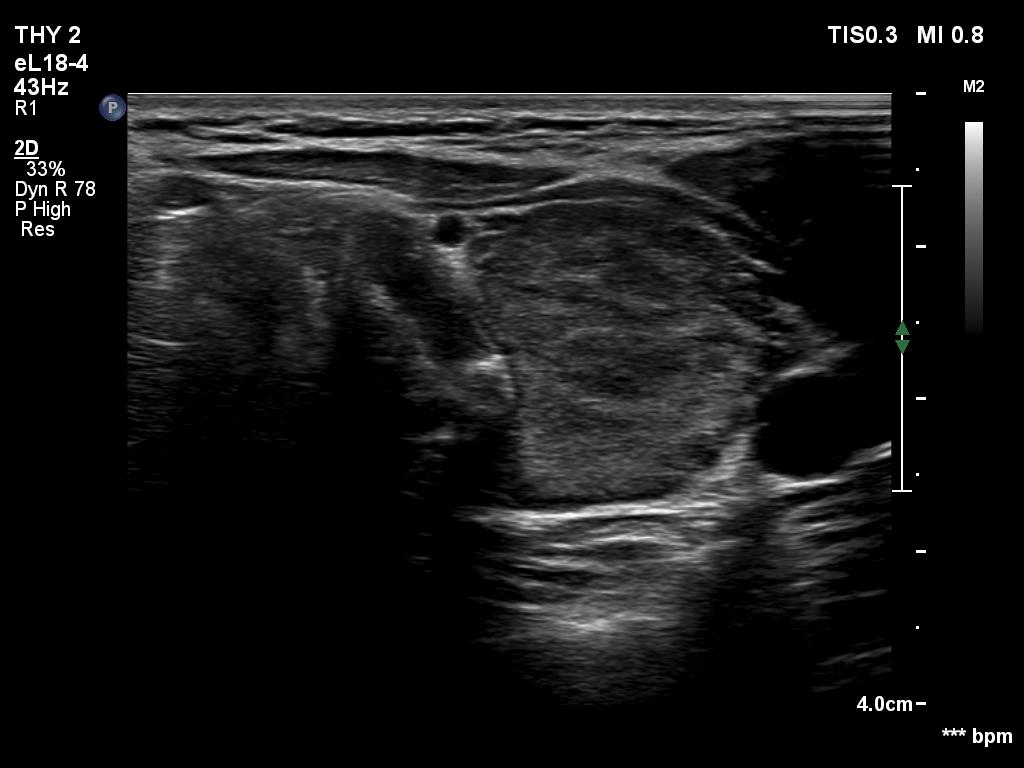

Right lobe, transverse scan

Right lobe, longitudinal scan